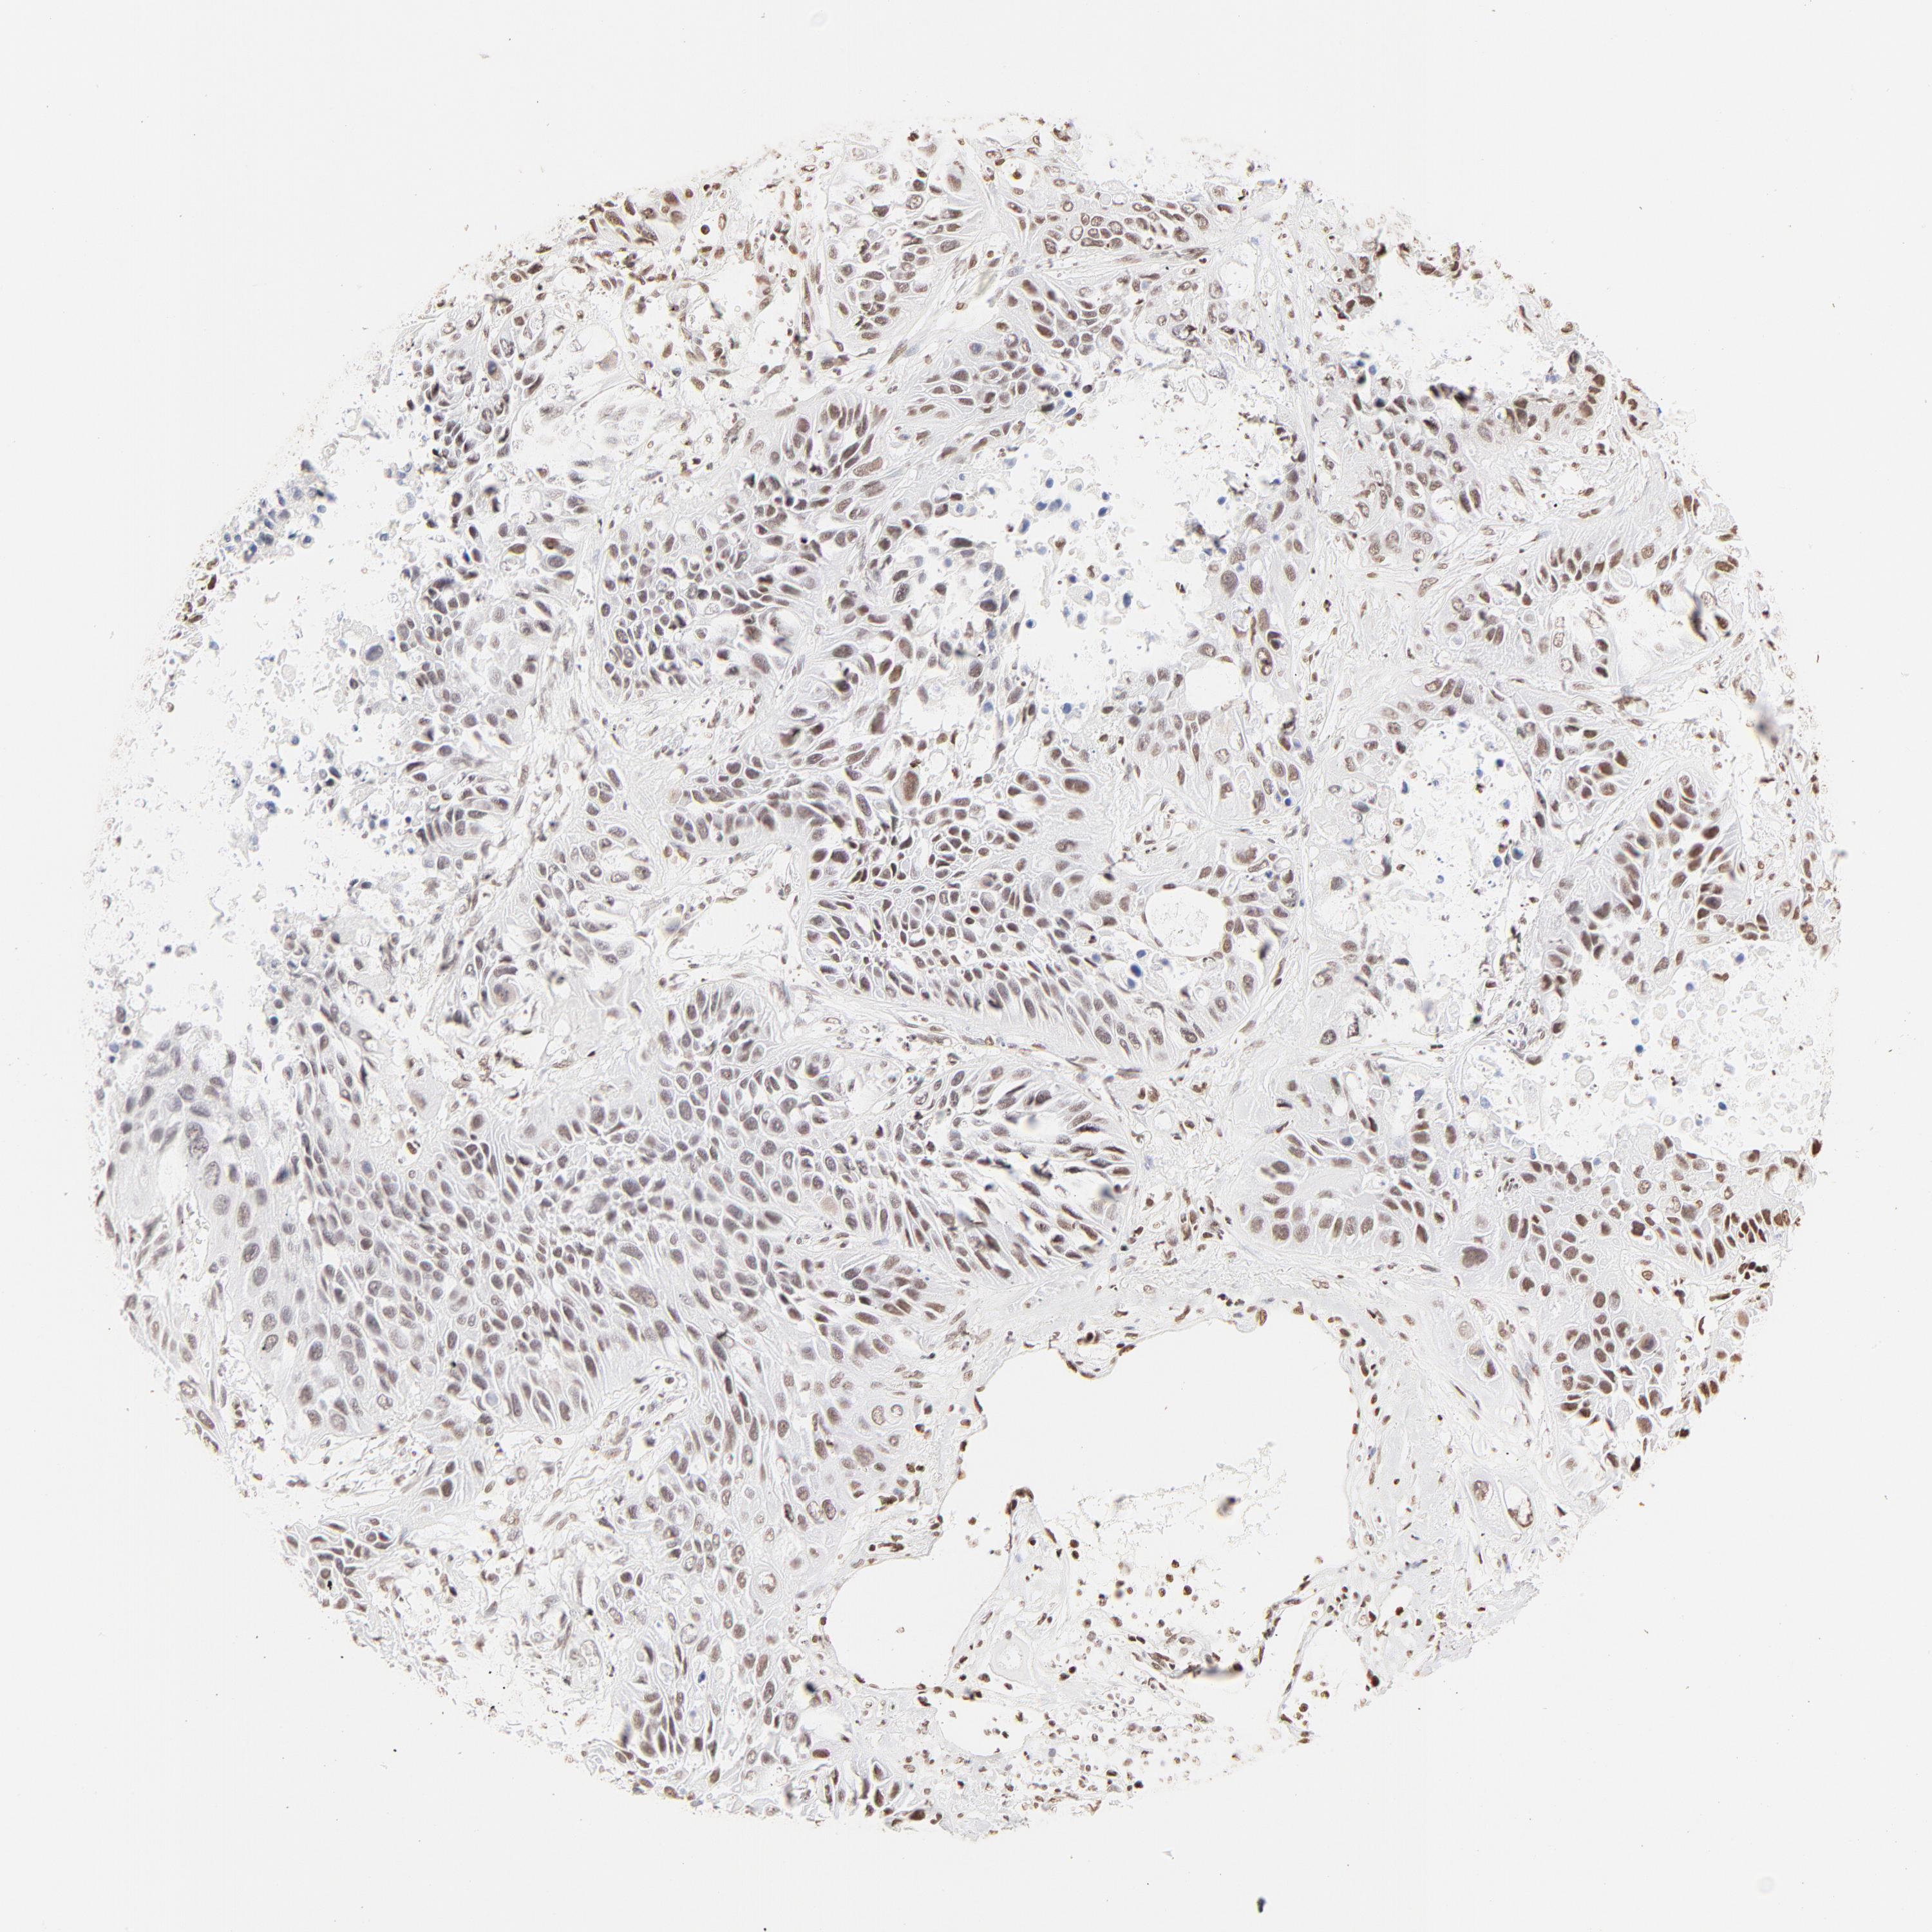

ZNF540 is potential prognostic, high expression is favorable in Lung Adenocarcinoma (validation)

Best expression cut offi

Based on the FPKM value of each gene, patients were classified into two groups and association between prognosis (survival) and gene expression (FPKM) was examined. The best expression cut-off refers the FPKM value that yields maximal difference with regard to survival between the two groups at the lowest log-rank P-value. Best expression cut-off was selected based on survival analysis .

When clicking on this number, the vertical dashed line indicating cut-off, the interactive survival plot, and the Kaplan-Meier curve will be adjusted to show results based on the best expression cut-off.

: 1.4

P scorei

Log-rank P value for Kaplan-Meier plot showing results from analysis of correlation between mRNA expression level and patient survival.

N/A

5-year survival highi

5-year survival for patients with higher expression than the expression cutoff.

For melanoma and glioma, 3-year survival is shown.

5-year survival lowi

5-year survival for patients with lower expression than the expression cutoff.

Average pTPM 2.5

Number of samples 105